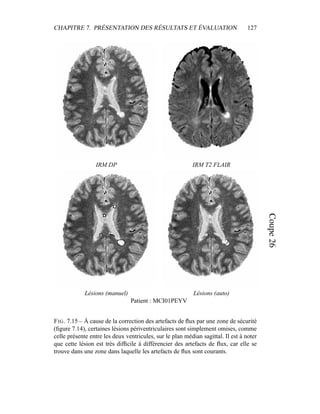

[42] G. Dugas-Phocion, M. A. González Ballester, C. Lebrun, S. Chanalet,

C. Bensa, G. Malandain, and N. Ayache. Hierarchical segmentation of

multiple sclerosis lesions in multi-sequence MRI. In International Sympo-

sium on Biomedical Imaging : From Nano to Macro (ISBI’04), Arlington,